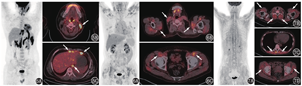

本例患者受累肌肉范围广泛,代谢不均匀,并且代谢增高区以骨骼肌表面的筋膜为主,部分肌肉有密度改变,因此考虑肌肉代谢增高的原因是病理性的。导致肌肉代谢增高的疾病有炎性病变和肿瘤性病变。肌肉原发良性肿瘤(如侵袭性纤维瘤、背部弹性纤维瘤、黏液瘤、横纹肌瘤等)和恶性肿瘤(如横纹肌肉瘤)的代谢可增高,良性病变的代谢通常低于恶性病变,且病变多单发[2]。骨骼肌转移瘤多表现为肌肉局灶性代谢增高,主要见于肺癌、肾细胞癌和结肠癌[1]。患者一般有明确病史,通常发生肌肉转移时肿瘤已全身广泛转移,PET/CT比较容易诊断。淋巴瘤累及肌肉较罕见,多为T细胞淋巴瘤,常见受累部位为大腿和上臂肌肉,可表现为局灶性肿块或弥漫性肌肉浸润,FDG摄取通常明显增高(图5)[2]。本例患者肌肉病变无明显占位效应,并且筋膜病灶比肌肉本身更重,既往也没有肿瘤病史,不支持肌肉肿瘤性病变的诊断。

肌肉感染或非感染性炎性反应也可以表现为肌肉代谢增高。结核性肌炎非常少见,仅占所有结核病的1%~3%[6],病原菌血行播散是其主要感染途径。结核性肌炎常起病隐匿,可表现为发热、局部包块、皮疹、肌痛、肌无力等,可累及几乎所有肌肉,常累及骨盆和下肢肌肉群。该病可伴全身其他脏器的结核病变,也可为单发[6]。FDG摄取与疾病炎性反应活动程度有关。结节病是一种原因不明的系统性疾病,病理特点是非干酪样肉芽肿性炎,病变FDG摄取非常高。结节病可累及全身各脏器,最常受累的是淋巴结和肺,肌肉受累少见[1,7]。皮肌炎是一种特发性炎性肌病,多数患者表现为肌无力和肌肉炎性反应,同时伴有特征性的皮肤损害,主要累及肩胛带肌和骨盆带肌,有时也可以累及颈部、喉部肌肉,甚至消化道肌肉和膈肌[8]。肌炎特异性抗体阳性可见于45%~85%的患者,与肌炎疾病的独特临床表型和组织病理学表现相关[9]。皮肌炎的肌肉病理学可见肌纤维变性、坏死,肌束膜区域和血管周围有明显炎性细胞浸润[10]。18F-FDG PET/CT表现为四肢近端肌肉及肢带肌对称性代谢增高(图6),代谢程度和累及范围与炎性反应累及程度和疾病活动度相关(图7)。